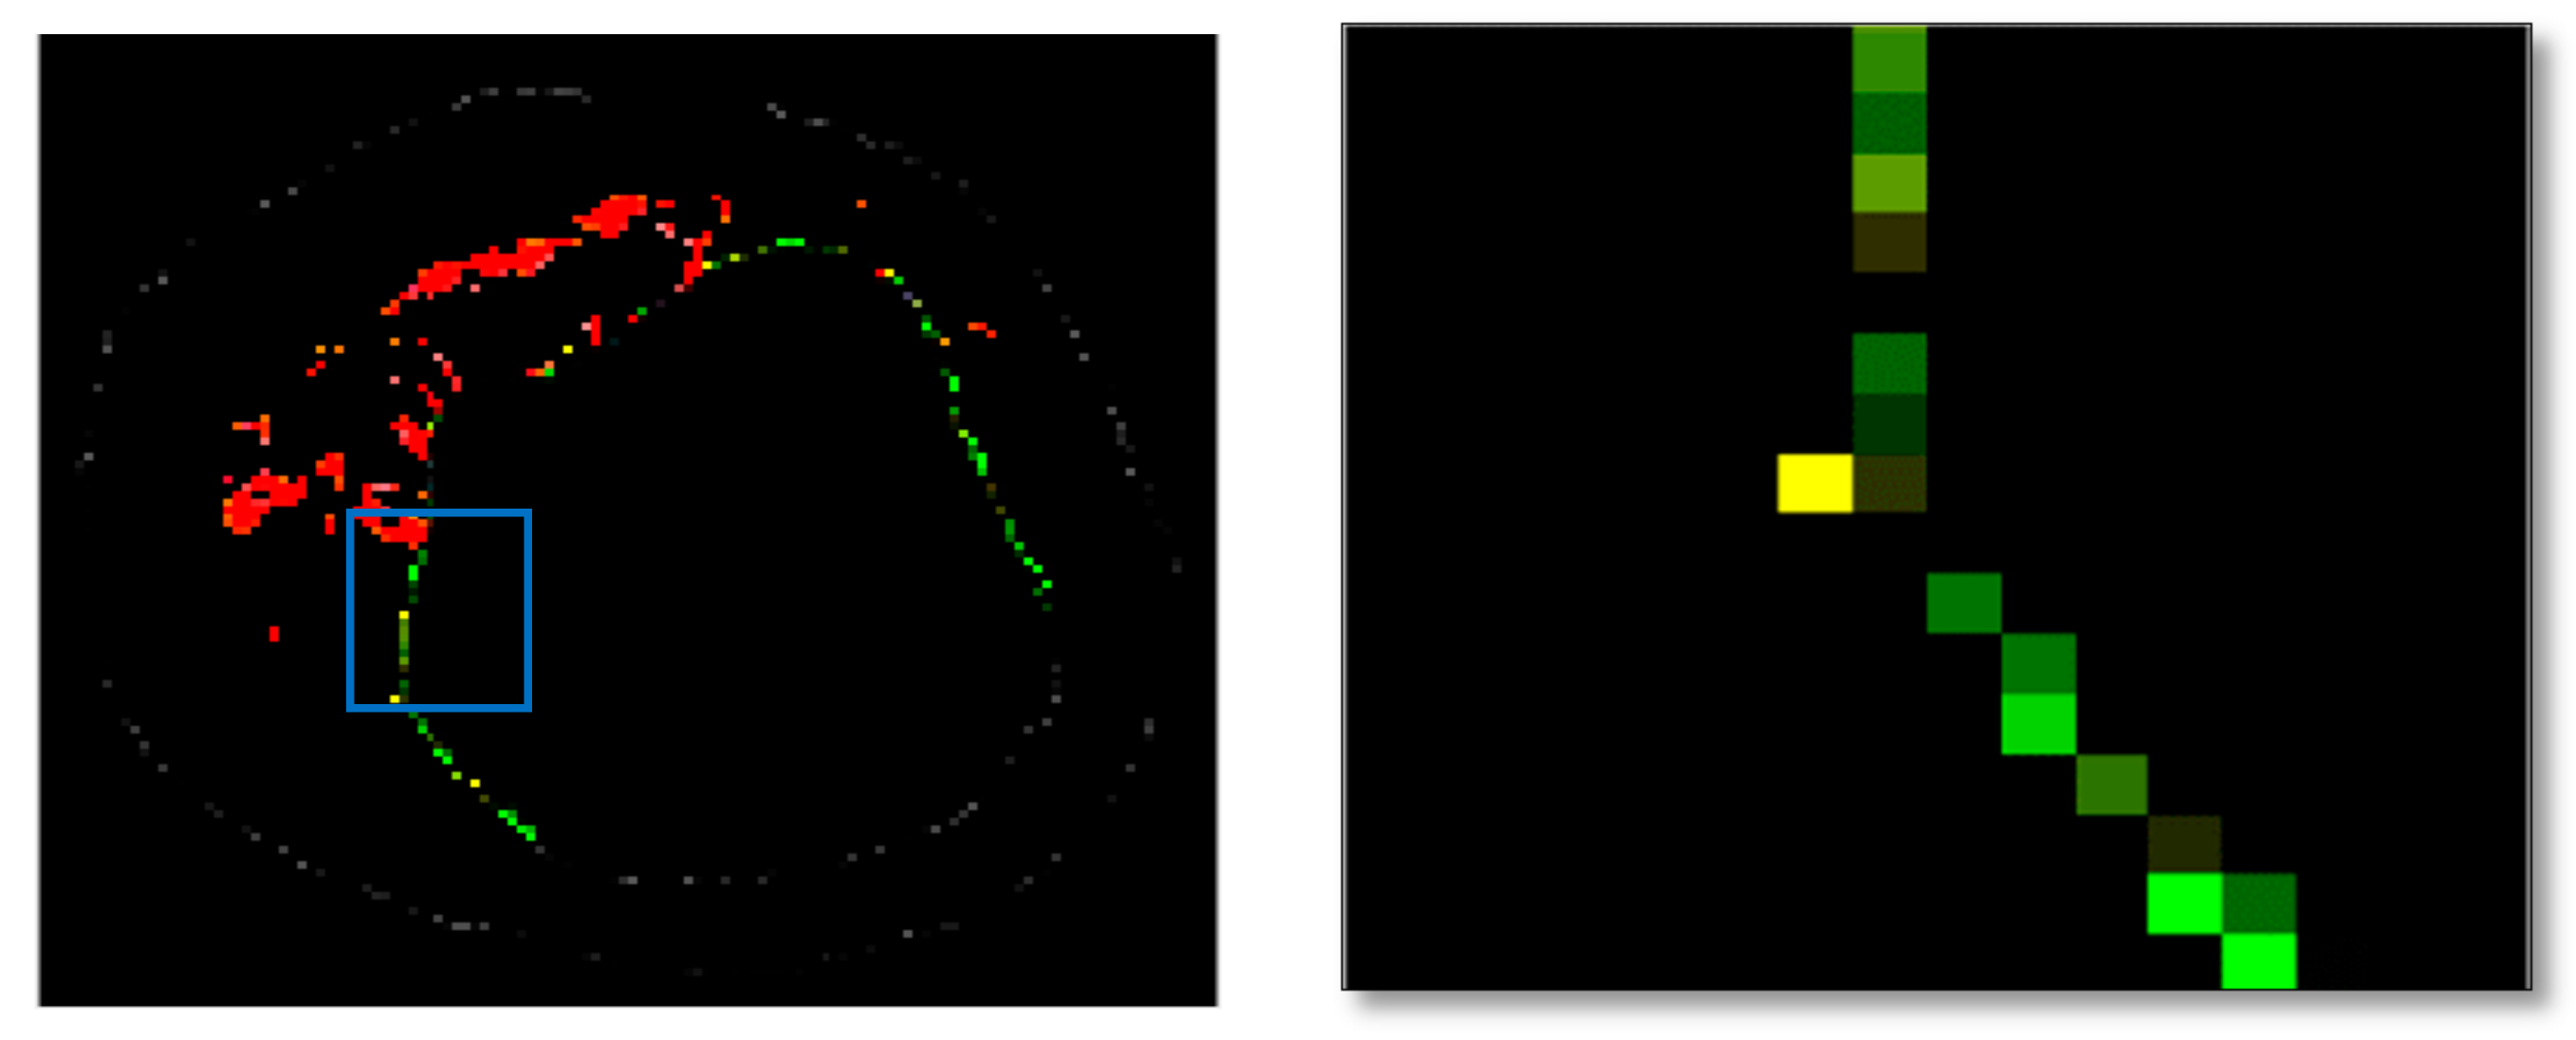

Previous studies have identified texture analysis as being useful in the analysis of ultrasound images. Plaque components appear with different texture patterns in IVUS images (Figure 11). Therefore, texture analysis methods are best suited to classifying pixels from plaque areas of IVUS images into three tissue classes, including dense calcium (DC), necrotic core (NC), and fibro-fatty (FF) [47].

Figure 11.

Different tissue types in the plaque area of IVUS images: (a) dense calcium, (b) necrotic core, and (c) fibro-fatty.

Grey-Level-based texture descriptors can be designed to reflect the different grey-level profile characteristics of the hard and soft plaque. Co-occurrence matrices describe the repeated occurrences of some grey-level configurations in the plaque texture classes. Run-length measures describe the maximum contiguous set of constant grey-level pixels located in a specified direction. A large number of neighbouring pixels of the same grey level represents a coarse texture, while a small number of these pixels represents a fine texture. Some microstructures of binary patterns in images can be detected by LBP [47]. According to the adapted algorithm by Taki [47], a higher overall accuracy was achieved by co-occurrence and LBP methods for characterising the fibro-lipid regions. Moreover, the run-length feature indicated a better capability for classifying DC plaques, while LBP and co-occurrence exhibited a better performance for NC. Texture descriptors such as LBP and MRL may miss useful information in grey levels of IVUS images, so grey-level information in combination with LBP and MRL features were employed to better classify the plaque types [20]. Because the best results on IVUS tissue characterisation were achieved using LBP, GLCM, and MRL, these three sets of features were used for the texture descriptor from the VH-IVUS images using the same data set.. These methods are explained in the following sub sections.